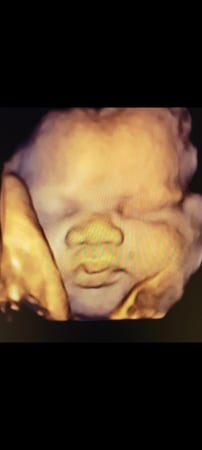

Tasha Crump, is registered by the American Registry of Diagnostic Medical Sonographers (ARDMS) and have over 18 years experience in medical diagnostic sonography specializing in Maternal Fetal Medicine. She is a highly proficient in the art of 3D 4D ultrasound. Tasha has practiced and trained in NYC's top ranked hospitals including Columbia Presbyterian. At Love at First Sight Imaging Studio you'll be in a very comfortable and calming atmosphere for you and your family to bond with your baby. We have state of the art equipment with HD Live to image unbelievably realistic views of your baby. You will fall in Love at First Sight.